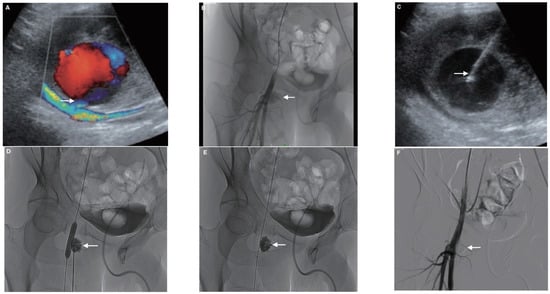

Figure 10. Example of a 62-year-old patient who developed a painful pulsatile mass with groin hematoma following coronary angioplasty. (A) Duplex ultrasound (US) at the groin puncture site demonstrated a large false aneurysm (FA) arising from the right proximal superficial femoral artery. (B) Angiography by crossover from the left side confirmed the FA from the superficial femoral artery (arrow). (C) The FA sac was then punctured under US guidance with a metallic needle with hyperechoic tip (arrow). (D) After inflating a MustangTM balloon of appropriate size in the parent artery in front of the FA neck in order to avoid reflux, a Glubran®2/lipiodol of a ratio of 1:1 was injected into the FA sac under fluoroscopic guidance until complete filling of the FA (arrow). (E) Arteriogram after deflating the balloon demonstrated, few minutes after glue injection, no NBCA migration (arrow). (F) Final angiography after embolization showed complete occlusion of the FA (arrow) and confirmed patency of the parent artery.